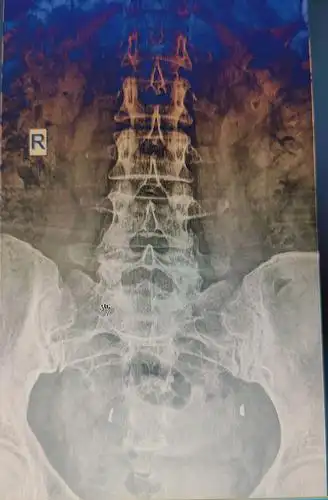

骶髂关节炎是什么原因引起的 这些医治方法可以有效缓解骶髂关节炎

骶髂关节错位评估

骶髂关节的评估与手法

强直造成的骶髂关节炎是什么?_辽宁京城强直医院

骶髂关节与慢性腰痛,这篇文章给你最好的解答!

长期女性顽固性腰腿痛,骶髂关节要重视

记录产后骶髂关节炎